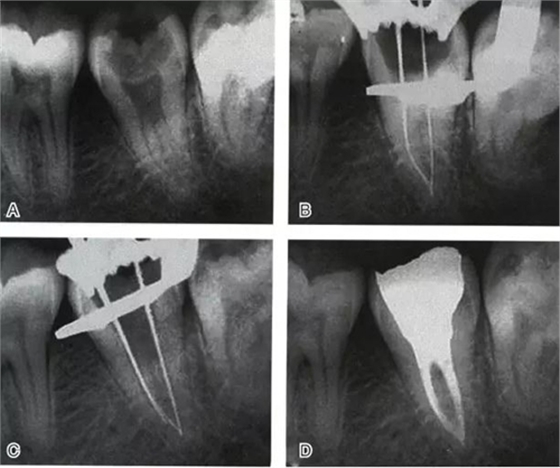

根管充填是C形根管治療成功與否的最重要因素。充填C形根管系統(tǒng)時(shí),近舌及遠(yuǎn)中根管可以進(jìn)行常規(guī)充填。關(guān)于狹區(qū)的充填,更適合以熱牙膠垂直加壓充填,這種方法可使牙膠到達(dá)根管系統(tǒng)的每一死角(圖4~7)。

圖5 Ⅰ型C形根管治療典型病例二,A:初始片,B:初尖銼片,C:主尖銼片,D:充填片